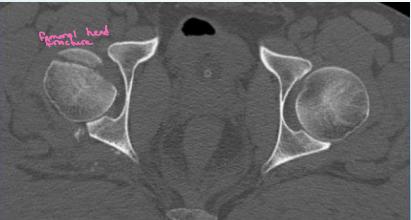

Imaging:

- X-ray & CT scan

- R/O an acetabular fracture (or intraarticular bony fragment)